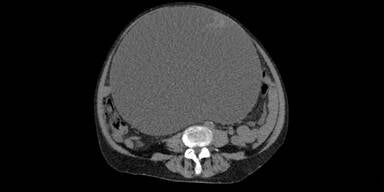

Klagenfurt. Ärzte des Klinikums Klagenfurt haben einen zehn Kilogramm schweren Tumor aus dem Bauch einer 73-jährigen Patientin entfernt. Wie der Krankenanstaltenbetreiber Kabeg am Donnerstag in einer Aussendung mitteilte, hatte die Frau wegen einer vermeintlichen Wasseransammlung in ihrem Bauch ihren Hausarzt konsultiert. Die Operation verlief erfolgreich - bereits fünf Tage nach der Operation konnte die 73-Jährige das Krankenhaus verlassen.

Die Diagnose im Klinikum Klagenfurt lautete auf Eierstockkrebs im Frühstadium. Die Entfernung des 10,2 Kilogramm schweren und im Durchmesser 30 Zentimeter großen Tumors verlief ohne Probleme: "Die Patientin benötigt weder eine Chemotherapie noch eine Strahlentherapie", erklärte Reinhard Mittermair, der Abteilungsvorstand der Allgemein- und Viszeralchirurgie am Klinikum Klagenfurt.